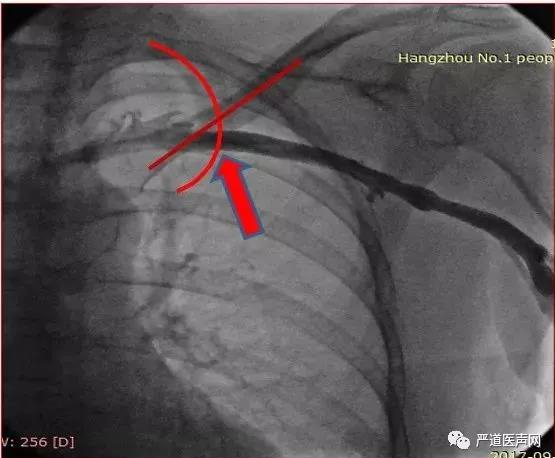

腋静脉穿刺位点:锁骨与第一前肋外交点的下方1.5-2cm

术中心房多次换位尝试,阈值始终偏高,许轶洲主任积极与学员分享交流处理策略,调整钢丝塑性,最终以阈值1.0v以下完成手术。